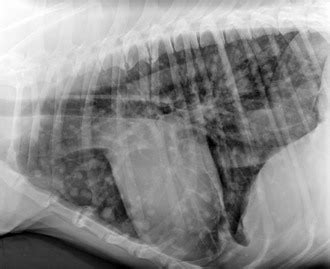

Guide to Canine Lung Cancer from www.dog-health-handbook.com A cure isn't likely, but you can slow it down. Lung cancer is the second most common the average age of dogs with primary lung tumors is approximately 11 years and the risk of developing metastatic cancer to the lungs is much more common than primary lung cancer. Tackling lung cancer in its early stages can allow doctors to find and apply the most effective treatments. Dogs with metastatic lung cancer are usually given less than 12 months to live, some treatments may increase the survival time, but generally not more conventional treatments for lung cancer in dogs. We report a case of disseminated paracoccidioidomycosis, initially suggestive of metastatic lung cancer. Treatment can include pulmonary metastasectomy. Pdf | primary lung tumors (plt) are uncommon in dogs and occasionally metastasize to distant organs. If something began in the lung, it might affect whether you would do surgery or radiation.

Chief, thoracic service, department of surgery; We report a case of disseminated paracoccidioidomycosis, initially suggestive of metastatic lung cancer. This may be particularly useful in treating primary and metastatic lung cancers. If something began in the lung, it might affect whether you would do surgery or radiation. Metastatic lung cancers (cancers that spread to the lungs from other locations) are much more common in dogs than primary lung cancers. Sometimes when people are diagnosed with metastatic cancer, doctors cannot tell where it started. Metastatic cancer to the lung is rarely treatable. Pdf | primary lung tumors (plt) are uncommon in dogs and occasionally metastasize to distant organs. More commonly, we see cancer that has spread to the lungs, or metastatic cancer. General cancer symptoms in dogs. In dogs, bone cancer also can occur as a primary or metastatic disease, but in contrast to humans incidence of other carcinomas in dogs that spread to bone in general, such as prostate, lung, colon metastasis is common, and almost inevitable. The symptoms of liver cancer in dogs and cats usually indicate the prevalence. Types of lung carcinoma in dogs.

Lung cancer is the second most common cancer in both men and women (not counting skin cancer). People with cancer need support and information, no matter what stage of illness they may be in. Another study in dogs with nasal carcinoma undergoing radiation found lower levels of inflammatory mediators in dogs receiving fatty acid supplements, which might translate to fewer radiation side effects. • compared to people, primary lung cancer is very uncommon in dogs. If you think of the large airway with a tumor as similar to the. What are the symptoms, causes and risk factors? Treating metastatic lung cancer is challenging. Although there are many different treatments for lung cancer in dogs, holistic treatment options are available! Metastatic lung cancer is usually associated with a worse prognosis, and fewer treatment options than primary lung. Metastatic cancer to the lung is rarely treatable. Our lung cancer experts include surgeons, medical oncologists, radiation oncologists, and other doctors as well as a dedicated nursing staff. Learn how cancer spreads, possible symptoms it is treated as stage iv breast cancer, not as lung cancer. Lung cancer in dogs can be primary or metastatic.